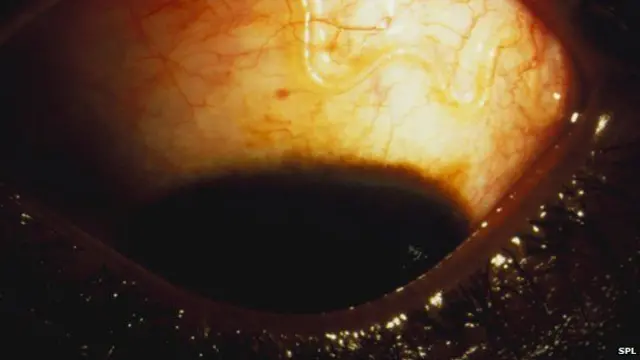

Verme no olho

Nos testes em Camarões, o sistema foi usado para detectar larvas de Loa Loa. Níveis altos deste parasita - que pode chegar até o olho - tornam arriscado o uso de ivermectina, um remédio comum contra vermes e parasitas, amplamente usado na África para tratar doenças como a oncocercose, também conhecida como "cegueira dos rios", e a elefantíase.